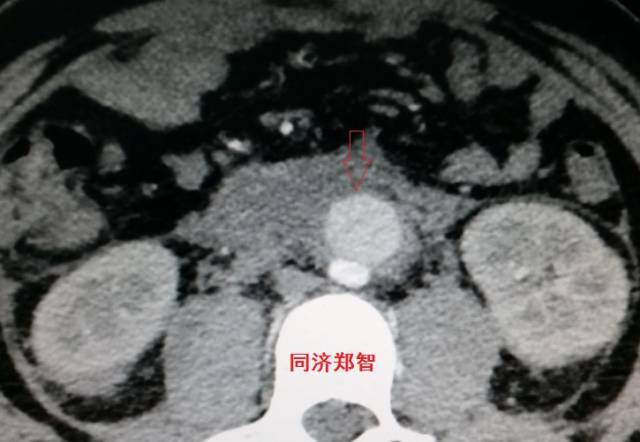

病例十

腹主动脉平扫CT提示正常外周一圈的钙化影中有内移的钙化影(红色箭头所示),CTA 证实为腹主动脉夹层。